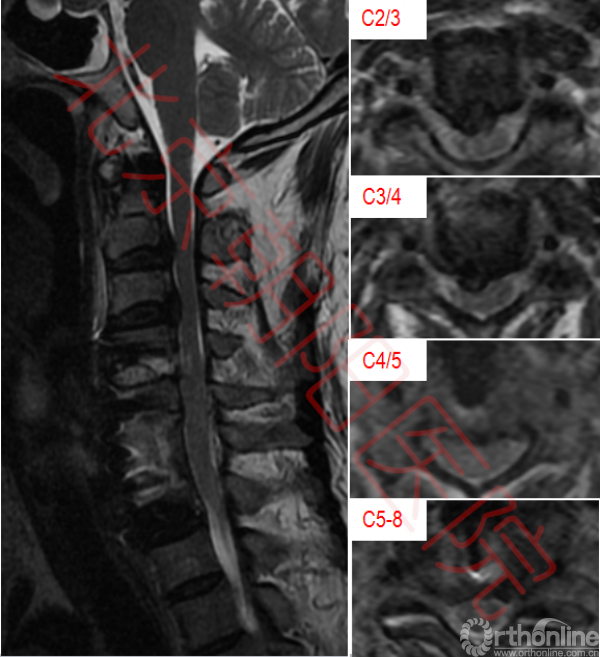

术后病理结果未见异常,细菌培养结果为耐甲氧西林金黄色葡萄球菌。继续应用利奈唑胺抗感染治疗。患者经术后3周抗感染及康复治疗,血常规、ESR、C反应蛋白PCT等感染指标恢复正常。上肢肌力较术前略有恢复,伸指肌、屈指肌、骨间肌肌力由I级恢复为II级;患者伤口愈合良好。术后2后复查颈椎CT(图4)显示植骨融合情况良好,颈椎核磁显示脊髓压迫解除。

图4:可见术后植骨融合良好

图5:C2/3、C3/4压迫仍存在,植骨节段脊髓压迫较术前明显改善